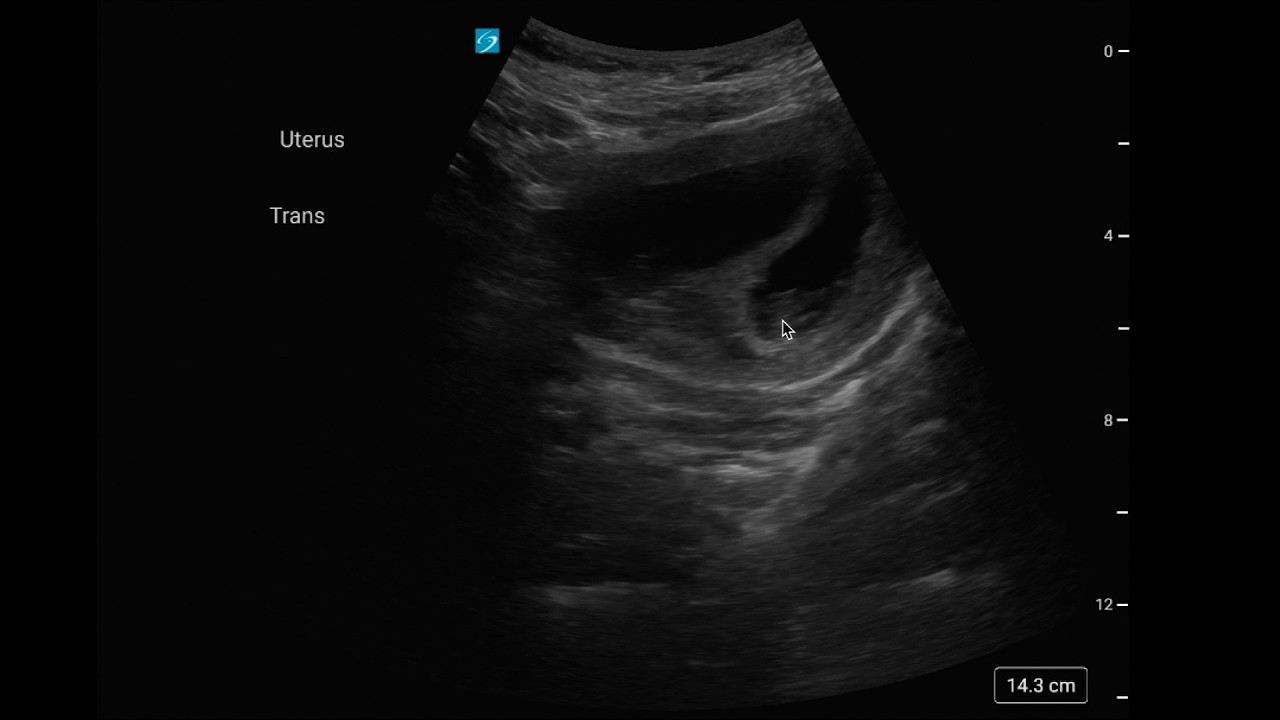

Identifying Retinal Detachment with POCUS

Описание: In this case, Dr. Jon Watson and Dr. Cierra Lewis review profound vision loss where ocular POCUS identifies a macula-off retinal detachment. They walk through eye ultrasound setup, avoiding excess pressure on the globe, classic retinal detachment appearance with optic nerve anchoring, and how to communicate critical findings to ophthalmology.

Soundbytes are short, digestible clips from the Soundcheck podcast, designed to deliver quick POCUS pearls you can take straight to the bedside.